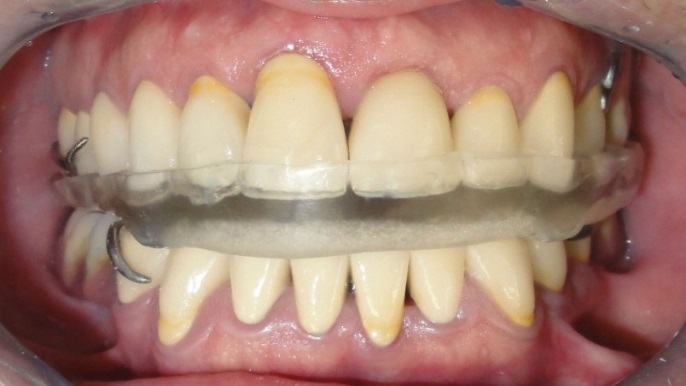

Interim restorations were fabricated after caries removal and primary preparation. The VDO was estimated using several methods, such as phonetics, inter-occlusal distance, and swallowing5. The restorations were cemented with non-eugenol zinc-oxide cement (DentoTemp, ITENA, France, Paris). A removable interim prosthesis was fabricated for the mandibular edentulous areas (Figs.6).

The patient used them for 3 months to adapt to it.

During the 3-month follow-up after the interim restorations, the available treatment options were thoroughly explained to the patient. Because of financial concerns, the patient could not afford the placement of dental implants in the edentulous areas. Therefore, the agreed treatment plan included the metal-ceramic complete cast crown of the teeth and the preparation of partial removable dental prostheses for the edentulous areas; the plan was that the patient would be able to financially afford the dental implants at a later date.

For the fabrication of partial removable dental prostheses, primary impressions were made of both jaws and custom acrylic trays were fabricated. The final impressions, after border molding, were made using medium-body addition silicone (Panasil, Kettenbach, Germany, Eschenburg). The frameworks were cast in a nickel–chromium alloy (Vera PDI, Aalba Dent Inc., Fairfield, CA) and the fit was checked intraorally. Finally, it was delivered to the patient. A hard occlusal splint was made to prevent nocturnal parafunctional occlusal wear